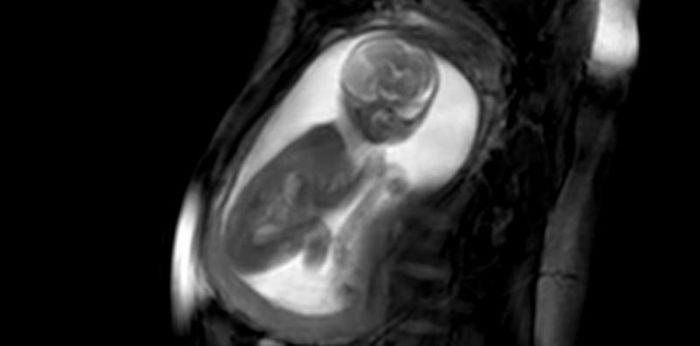

The anatomy ultrasound is not only valuable for health professionals, but also allows mums and dads to clearly see their unborn child.

One of the most exciting moments as an expecting mum or dad is to see your unborn child’s first few movements inside the womb. But these are usually very grainy images, plus you need the help of a doctor to get a good look at your child.

But through the help of new technology called anatomy ultrasound, you will now be able to clearly see your child moving inside the womb!

The ‘Anatomy Ultrasound’ Lets Doctors Capture the Most Amazing Images!

The anatomy ultrasound was developed by researchers and clinicians at the iFind project. The project aims to “allow screening of foetal abnormalities in an automated and uniform fashion.”

Researchers developed it using techniques in ultrasound, MRI, robotics, and computing. This combination of technologies makes it possible to capture the most amazing images and videos. These images are the clearest so far.

Another important point is that this type of ultrasound is safe to use in pregnancies, potentially making it a better option for mums in the future.

Looking at the videos, the images are pretty clear and spectacular!